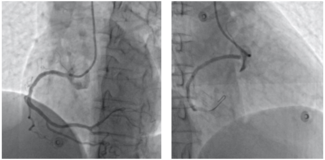

A 57-year-old woman with good past health attended the accident and emergency department at an outside hospital for sudden onset chest pain. Electrocardiogram revealed ST-segment elevation at inferior leads.